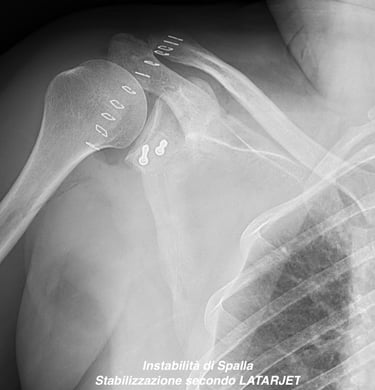

Instabilità di spalla

Gallery

Attività Chirurgica